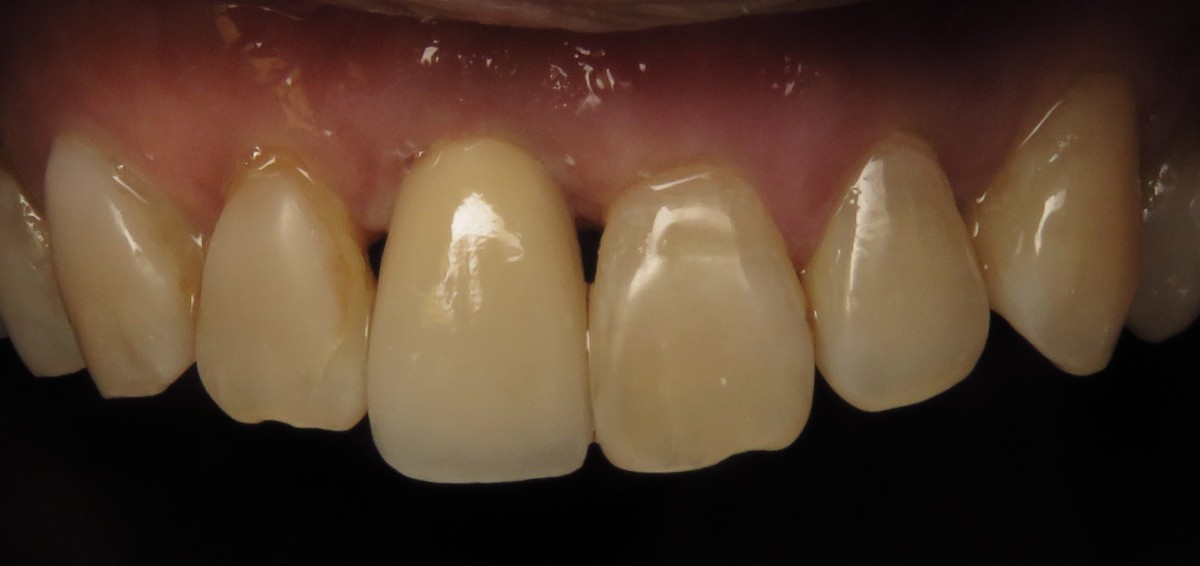

Four months after implant placement the patient returned for evaluation of the implant and final prosthetic procedures. Clinically the soft tissues looked healthy and pink, despite the poor oral hygiene (Figure 7). Bone levels were also stable and improved since placement. RFA measurements were at 69 bucco-lingually and 66 mesio-distally, showing an increase since placement. A closed tray impression coping was used to capture the position of the implant and surrounding structures. To fabricate the final restoration, a prefabricated zirconia abutment was used with 15-degree angle correction (Figure 9). The lab modified the abutment as needed and fabricated a cement retained final layered zirconia crown. Caution was taken to minimize excess cement (Figure 10) and deliver a well-fitting all-ceramic restoration over a ceramic implant (Figure 11).